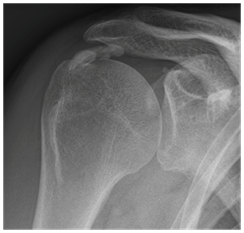

The pillars in the conservative treatment of calcifying tendinopathy are nonsteroidal anti-inflammatory drugs, physiotherapy and prudent use of subacromial corticosteroid injections (SAI). These non-operative therapies are effective in approximately 70% of individuals with calcifying tendinopathy.9 Ultrasound (US) guided needling and extracorporeal shockwave therapy (ESWT) have been proven to be successful minimally invasive treatment modalities when conservative treatment fails (Figure 1 & 2).10,11 Never- theless, failure of these nonsurgical therapies may necessitate surgical treatment in some cases.12

All US-guided needling procedures were performed by an experienced radiologist with a single needle technique without lavage or aspiration. This is common because the goal of fragmenting the calcific depot ensures surface increasement and helps the tendon to remove the calcification itself.14,17,18 The pro- cedure was performed by sterile technique and surgical gloves. First, a diagnostic US examination in the sitting position was performed to evaluate the location and size of the calcific deposits and the integrity of the rotator cuff in the affected shoulder. The skin was then cleaned with a 10% iodine solution and anti- septically draped. After administration of local anesthesia (10cc, 2% lidocaine), the calcific deposit was punctured 10-15 times with a hyperdermic needle under real-time monitoring with US (Figure 3 & 4). There is no evident preference for the used technique,11 single-needling is used in about 50% of recent studies, hence a prevailing technique.19 The final step in the procedure was an injection of a bupiva- caine 0.5% kenacort 10 mg/ml (7:3) mixture into the subacromial space under US guidance.